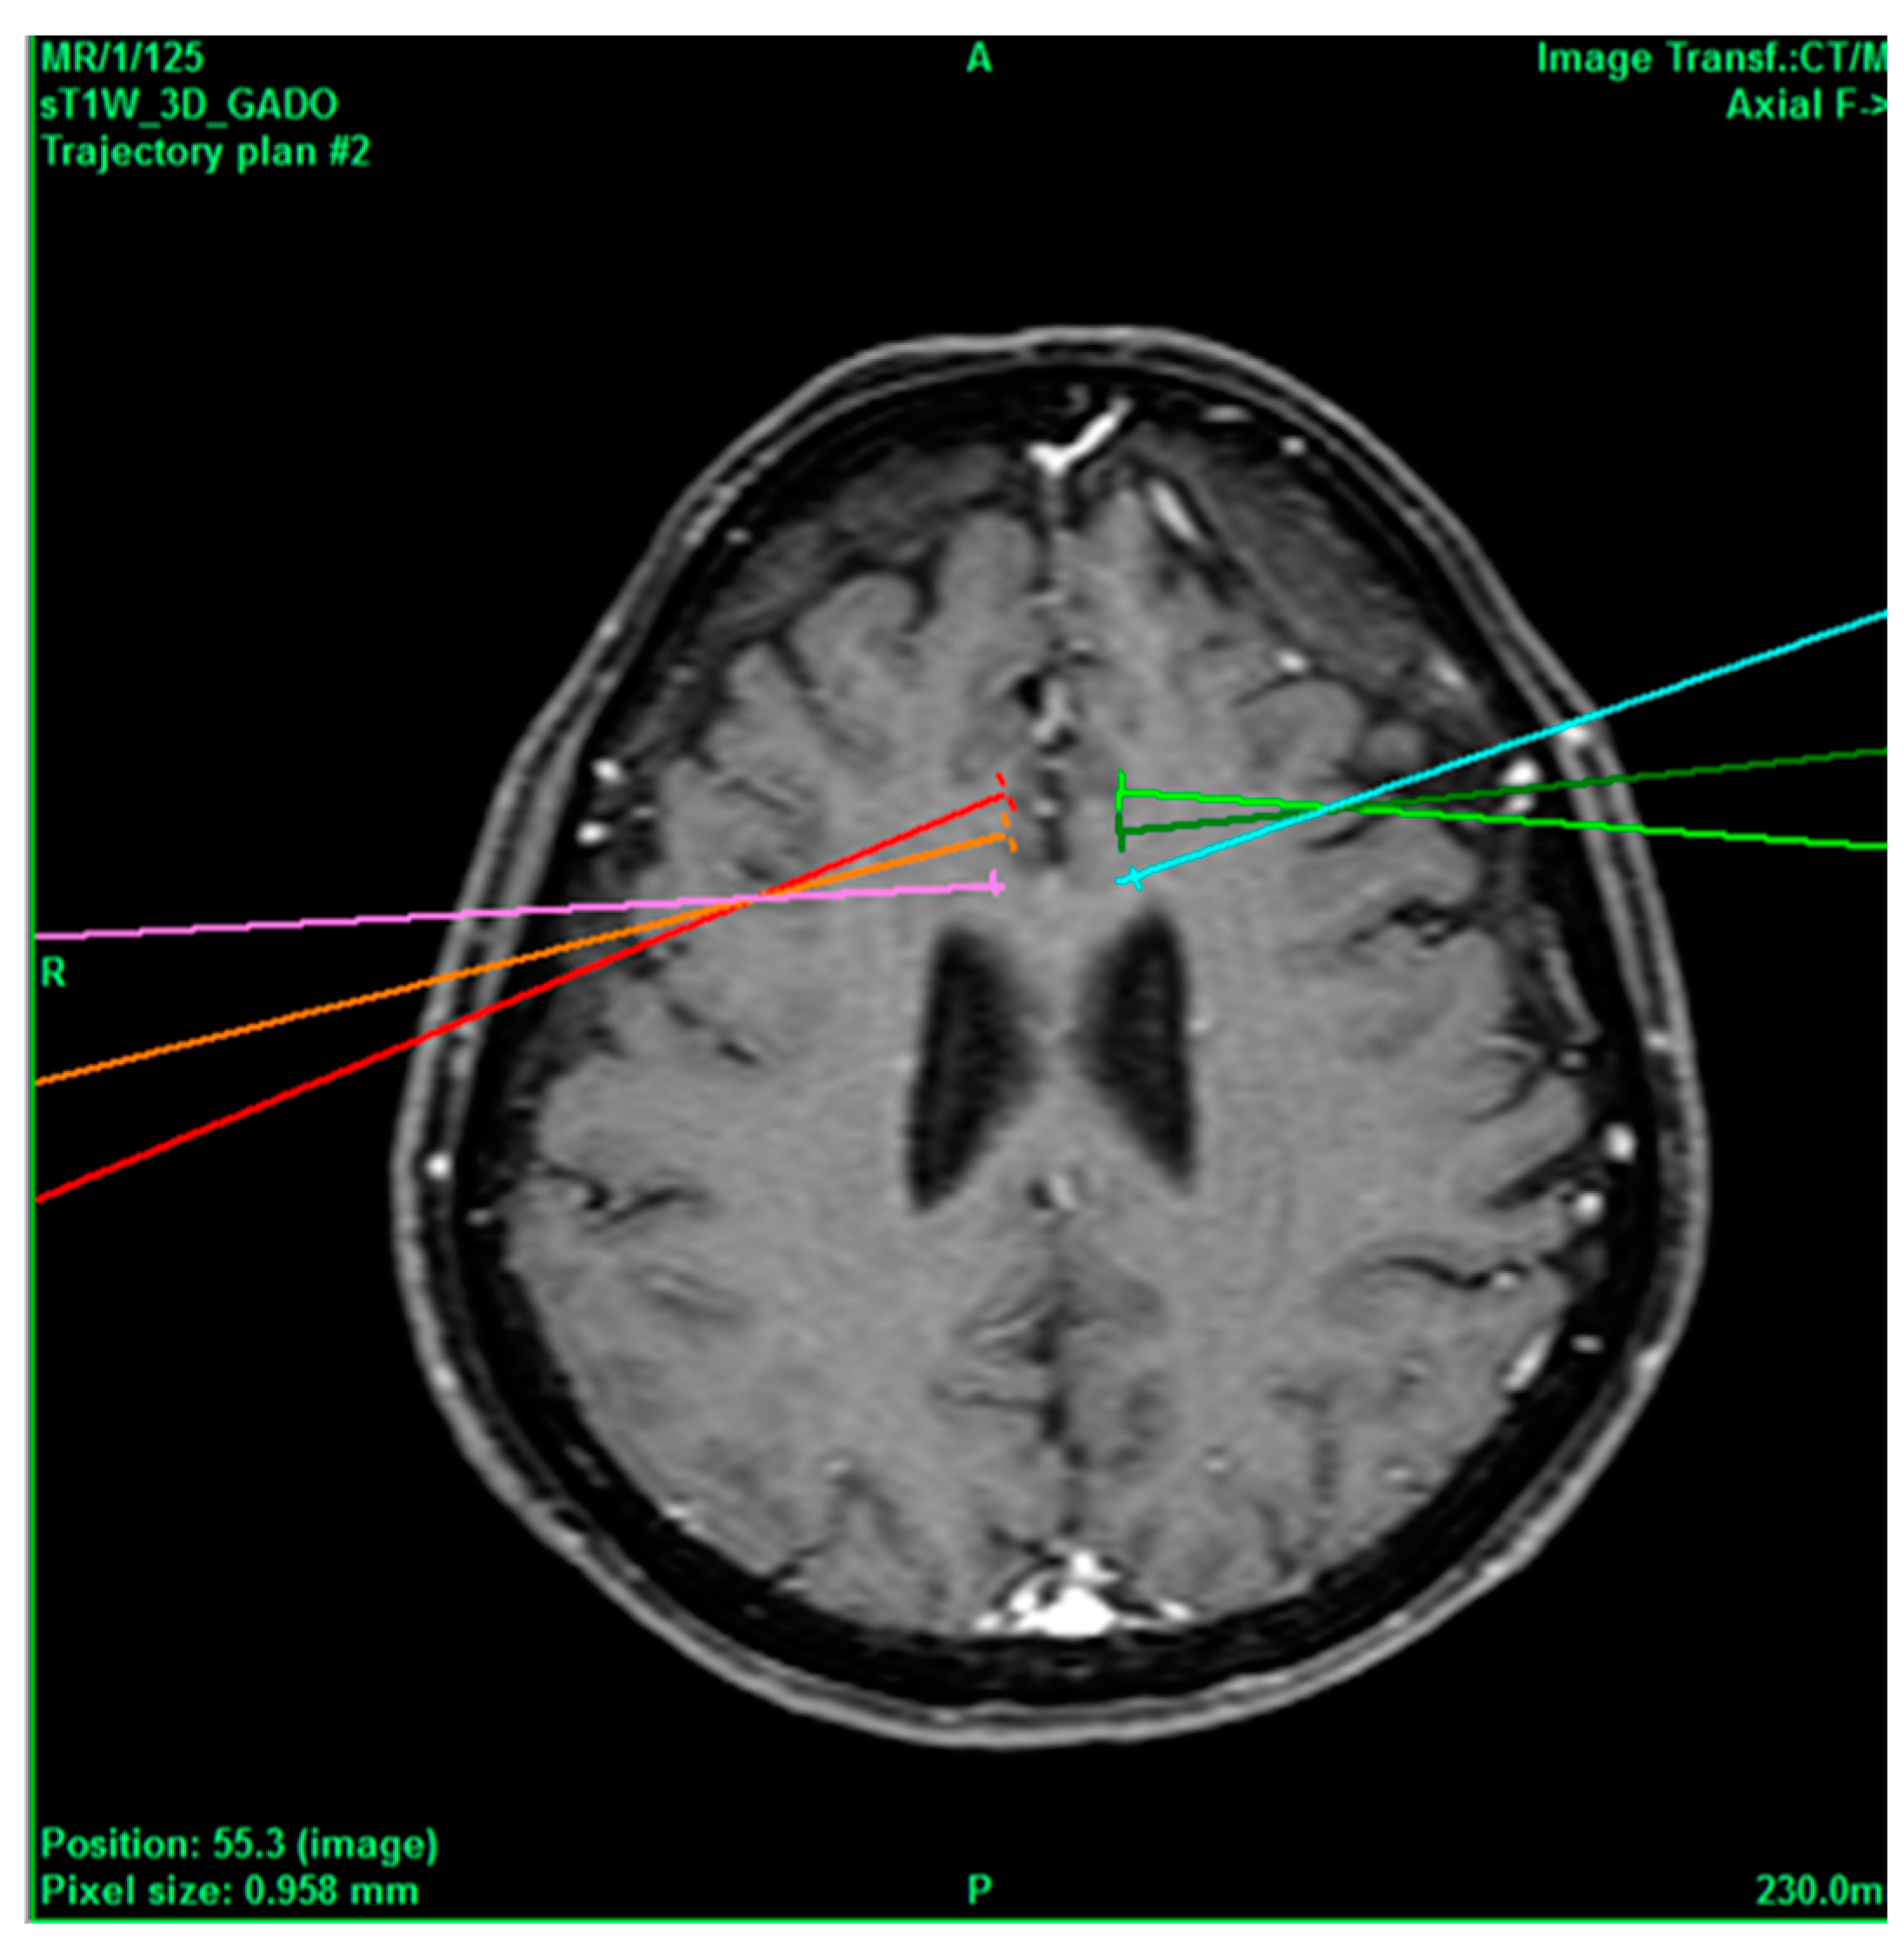

Figure 2.

Bilateral projection of cross-sectional cingulotomy from patient 1.